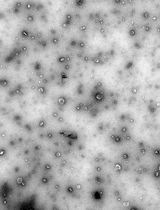

Dynamic light scattering analysis showed that the average sizes for blank nLNPs (Figure 3) and IL-22/nLNPs (Figure 5) are 189.9 ± 69.3 and 184.2 ± 84.96 nm, respectively, based on triplicate measurement.

Figure 5. Measurement of size in IL-22/nLNPs. Particle size of IL-22/nLNPs was 184.2 ± 84.96 nm in diameter.